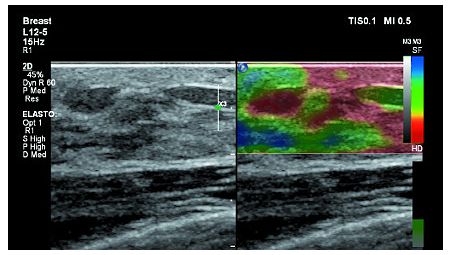

Система Affiniti 70 оснащена датчиками PureWave, которые позволяют увеличить глубину проникновения при сканировании сложных пациентов. В результате, один и тот же датчик можно использовать для диагностики пациентов различного телосложения. Благодаря точному формированию луча система помогает обеспечить превосходное пространственное и контрастное разрешения, высокую однородность отображения тканей, а также низкие уровни артефактов и шума на изображении.